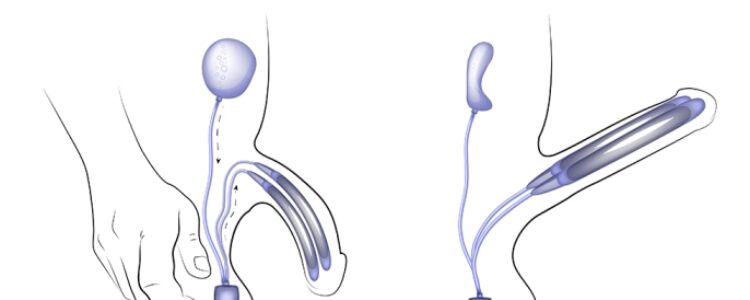

A malleable penile implant is a type of surgical device used to treat erectile dysfunction. It consists of two flexible rods that are implanted into the penis, allowing the patient to manually position the penis for sexual activity. Malleable implants are a popular choice for individuals who are unable to achieve or maintain an erection through other treatment methods.